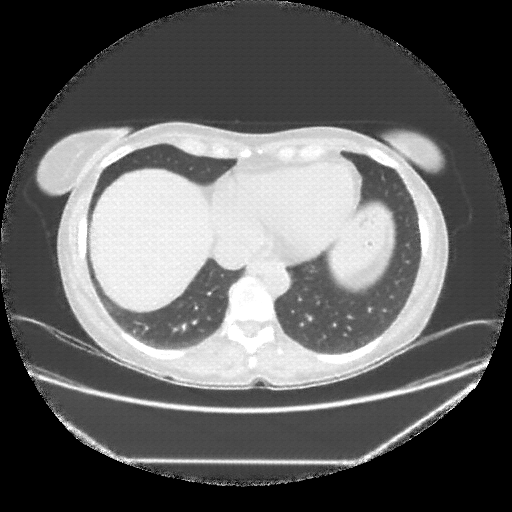

Image Grid

4Γ—3 grid: Rows show different image types (Original NATIVE, Reconstructed NATIVE, Original VENOUS, Generated VENOUS), Columns show windowing techniques (No Window, Lung Window, Mediastinum Window)

Original VENOUS CT scan

Full window (WL 1023.5, WW 4095 β†’ Low βˆ’1024, High +3071)